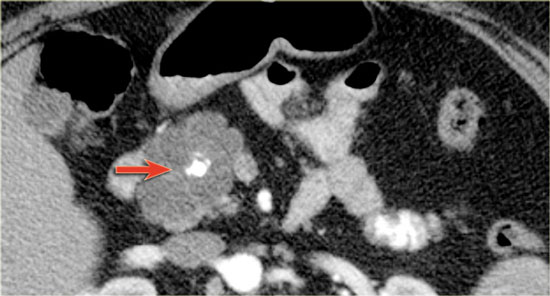

CT-image of a 51 year old woman with a history of gallstones and abdominal pain.

There is a hypodense lesion with central calcification in the head of the pancreas.

The lesion has a lobulated contour.

Continue with the MR.

MRI better demonstrates the morphologic features of the lesion (fig).

On T2WI the lesion is multicystic.

Note the central low signal due to the central scar with calcifications.

Although some of the cysts are rather large, this is still a characteristic appearance of a serous cystic adenoma (macrocystic form).